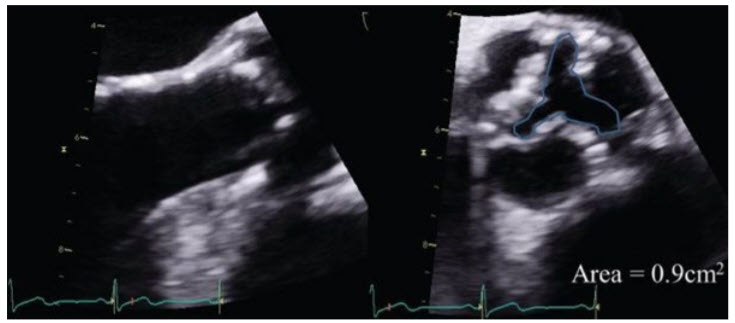

A 76-year-old woman is referred to your clinic with recent onset of exertional chest pain. She has a long-standing history of hypertension and atrial fibrillation. On examination, her body surface area is 2.0 m2 , BP is 150/100 mmHg, and heart rate is 80 to 90 bpm and irregular. The carotid upstroke is delayed and diminished. The apex beat is nondisplaced but sustained. S1 is normal, and S2 is soft and paradoxically split. There is a grade II/VI ejection systolic murmur heard best at the right upper sternal border that radiates to the carotids. An echocardiogram reports normal ejection fraction with a stroke volume of 55 mL. The peak and mean gradients across the aortic valve are 44/28 mmHg. The dimensionless index is 0.21 and the calculated aortic valve area is 0.83 cm2 . You review the echocardiogram (Fig. below)

and confirm the accuracy of the left ventricular outflow tract (LVOT) diameter and are satisfied that multiple windows were used to obtain the gradients.